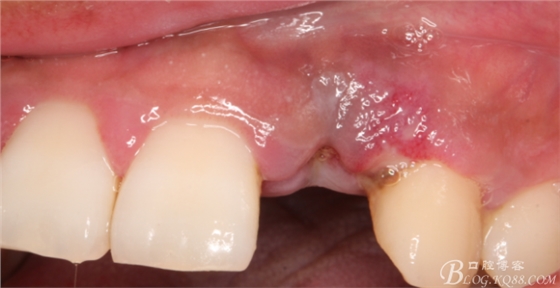

10天拆線一切正常,又過了兩周患者復(fù)診,自述期間無異常??趦?nèi)檢查,真的嚇了一跳,唇側(cè)鼓了個(gè)包,擠壓有白色分泌物溢出,絕對(duì)不是膿液,液體排除后,術(shù)區(qū)觸診空虛,外觀塌陷。這時(shí)候考研大夫的時(shí)刻到了,是先觀察一段時(shí)間再說?還是馬上進(jìn)行處理?我的回答是:馬上處理!如果你沒有及時(shí)處理,而是放患者回家觀察,那么接下來會(huì)發(fā)生如下情況:1.回家后患者家屬及親友會(huì)有很多你可以想象得到的討論;2.患者及家屬會(huì)對(duì)你產(chǎn)生不信任,勢(shì)必會(huì)到其他門診或醫(yī)院檢查,他院大夫會(huì)不會(huì)發(fā)表對(duì)你不利的言論;3甚至?xí)蚁嚓P(guān)法律界人士找你討要說法。